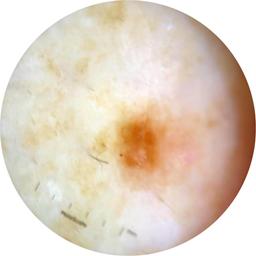

ISIC_9472333

Information

2057 x 2057

Clinical

Field Value

acquisition_day 230

age_approx 65

anatom_site_1 Trunk

anatom_site_2 Anterior trunk

anatom_site_general anterior torso

concomitant_biopsy False

diagnosis_1 Benign

diagnosis_confirm_type single image expert consensus

family_hx_mm True

fitzpatrick_skin_type I

image_manipulation instrument only

image_type dermoscopic

lesion_id IL_9967494

patient_id IP_4296977

personal_hx_mm True

sex female